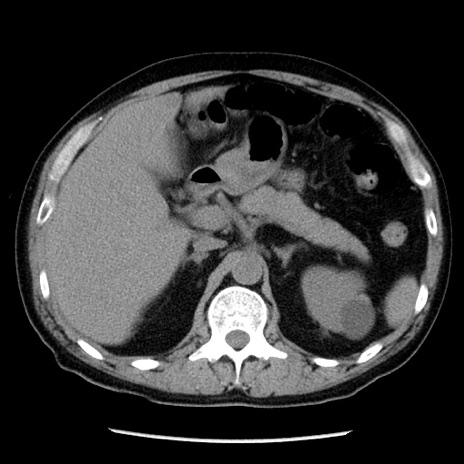

症例29(横断像)

【症例】40歳代男性

【現病歴】2日前から胃痛あり。徐々に周期的な激痛に変化した。本日になっても激痛があるため受診。

【身体所見】意識清明、BT 38-39℃台あり、腹部:膨満、やや硬、右下腹部に圧痛あり。

【データ】WBC 8500、CRP 23.26